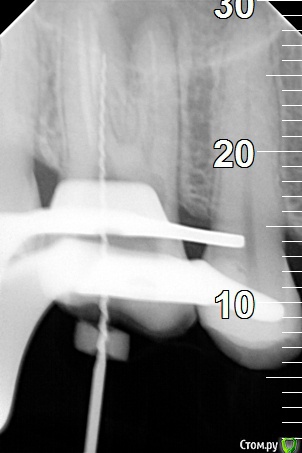

Sier10 Опубликовано 15 марта, 2020 Поделиться Опубликовано 15 марта, 2020 Здравствуйте. Отдельную тему создавать не стал, так как название темы было бы аналогичным) Давно читаю форум, извлёк много полезной информации здесь, за что всем старожилам большое спасибо. Последние два дня выделись для меня очень печальными. Позавчера отлатералил пульпитный 47з. В медиальной системе в обоих каналах не довёл по 2-2,5мм, была проблема с определением рабочей длины, аплок показывал 0, плюс пациент устал сидеть больше 3часов в кресле,, но это все отговорки, своей вины и глупости я не отрицаю . Недоведение я осознал уже после того как отправил пациента с запакованными каналами и временной пломбой, когда пересматривал снимки.. естественно, пациенту все объясню и перепакую (если он меня не пошлёт куда подальше), и по этому поводу меня интересует, стоит ли держать зуб на кальции перед повторным пломбированием? Пульпарную камеру раскрывал с уже наложенным кофердамом, в протоколе гипохлоран, медиальную систему активировал гуттаперчевым штифтом, дистальный канал - эндочак. Снимки на работе, завтра скину сюда, если нужно. Ссылка на комментарий

Sier10 Опубликовано 15 марта, 2020 Поделиться Опубликовано 15 марта, 2020 А вчера на распломбировке 16з, впервые нарезал перфорацию. Работал, как обычно при распломбировке, протейперами д3 и ручными файлами, используя сольвент. Мб и нёбный каналы шли хорошо, но в дб дальше устья дело не шло и в какой то момент протейпер слишком уж резво начал резать, и пациенту стало больно. Воткнул бумажный штифт - немного кровит на кончике, но в Канале гуттаперча никуда не делась. 35 н-файл в нарезанный тонель и пошли на снимок. Увидел, что у нас перфорация, немного запаниковал, положил кальций, тефлон и временная пломба. Все объяснил пациенту, отправил на микроскоп для закрытия перфорации.Я так понимаю, что при обработке в прошлый раз чрезмерно расширили и выпрямили канал, истончив его медиальную стенку? И я во время работы где то чрезмерно приложился, наверное, как раз в этом истонченном месте и сделал перфорацию, я правильно понимаю? Помогите понять причину, пожалуйста9696B58D-E577-4BB9-8E1F-C40822CEBB98.bmp6954AB4B-1B97-40B6-901B-BA4983603E7B.bmp Ссылка на комментарий